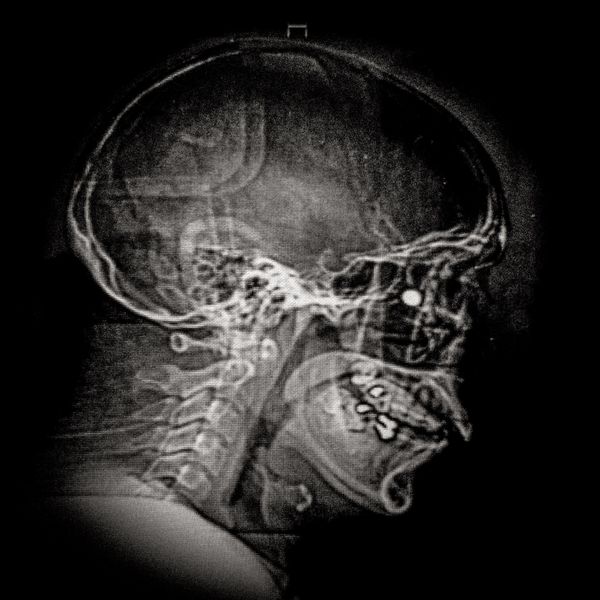

460 people have been seriously injured in their eyes, 34 of whom suffered total loss due to the indiscriminate use of pellets and tear gas bombs by the Carabineros de Chile special forces. The Carabineros fired their rubber bullets and tear gas guns directly into the faces of the protesters during the Chilean social outbreak between late 2019 and early 2020. This figure has made Chile the country with the world record for eye mutilation by state and security forces.

By early March 2020, around 3,838 people had been injured and according to the Chilean Society of Ophthalmologists and human rights organizations, 460 of them ended up with serious eye complications, loss of the eyeball, and also loss of sight. This figure has made Chile a world record for eye mutilation, due to the indiscriminate use of pellets and tear gas bombs by special forces of the Carabineros, who have shot their weapons directly into the faces of the protesters.